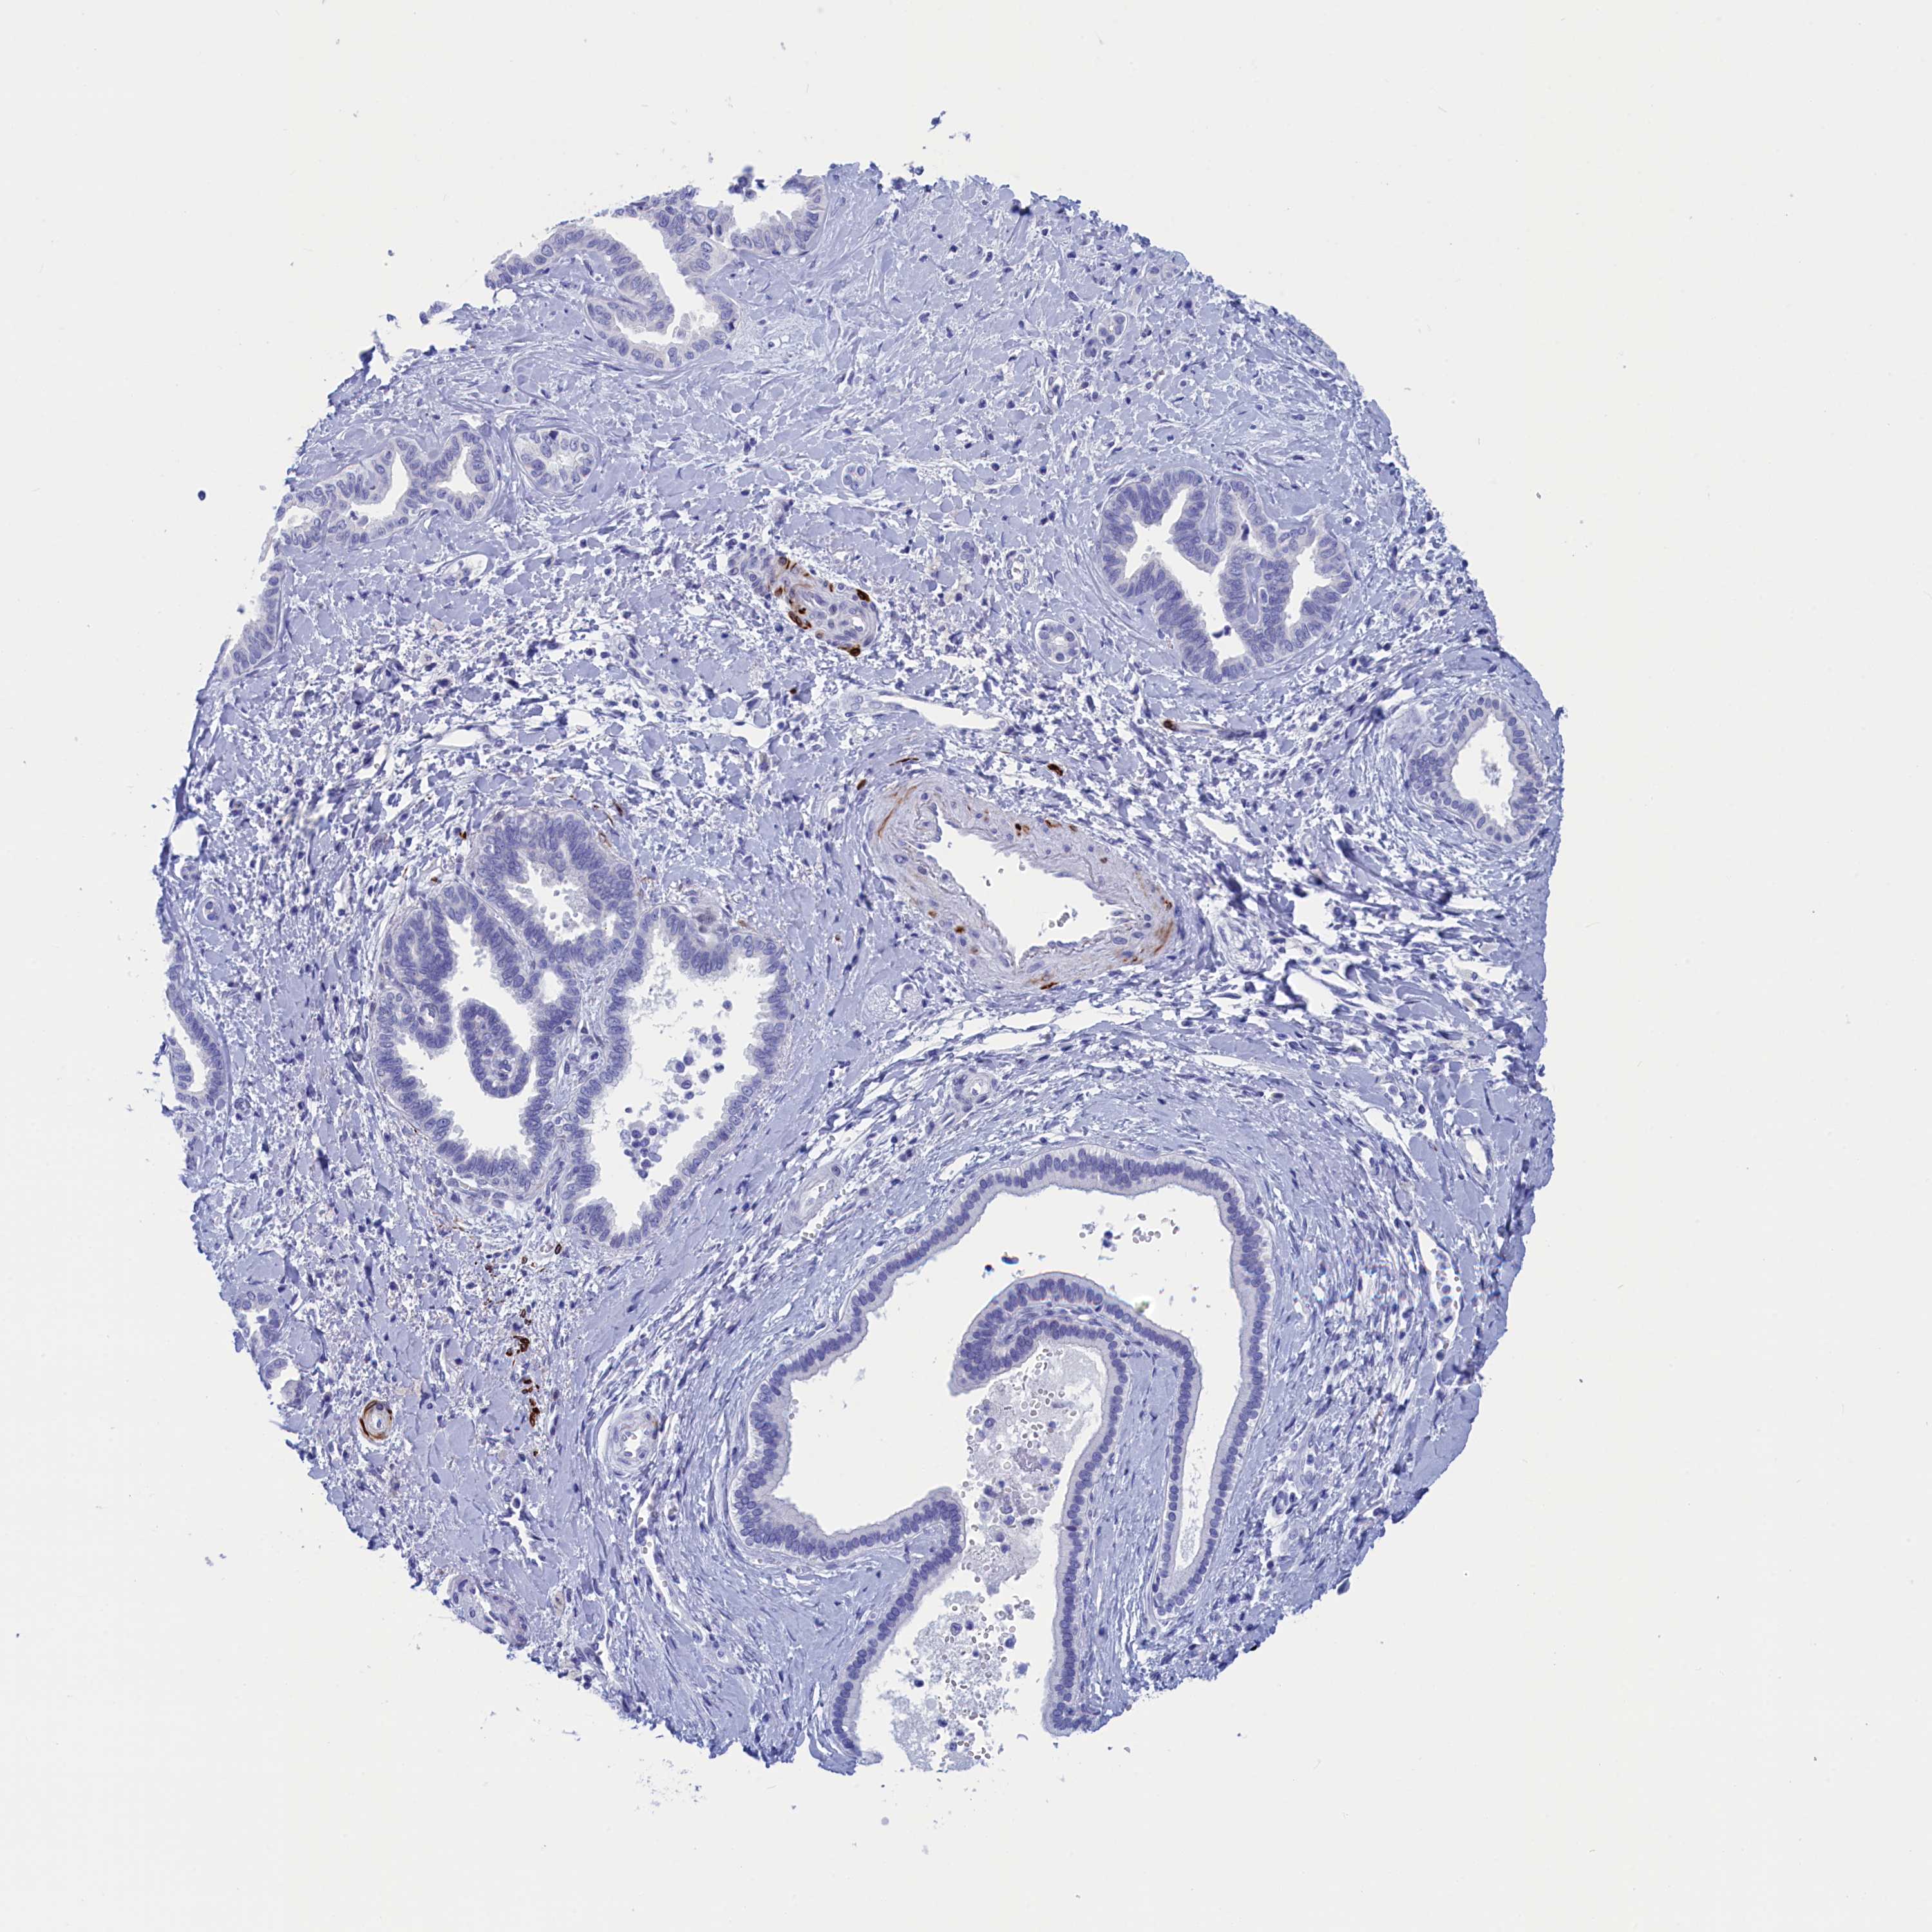

LIVER CANCER - Protein expressioni

A mouse-over function shows sample information and annotation data. Click on an image to view it in a full screen mode. Samples can be filtered based on level of antibody staining by selecting one or several of the following categories: high, medium, low and not detected. The assay and annotation is described here.

Note that samples used for immunohistochemistry by the Human Protein Atlas do not correspond to samples in the TCGA dataset.

Antibody stainingi

Antibody staining in the annotated cell types in the current human tissue is reported as not detected, low, medium, or high, based on conventional immunohistochemistry profiling in selected tissues. This score is based on the combination of the staining intensity and fraction of stained cells.

Each image is clickable and will lead to virtual microscopy that enables deeper exploration of all samples and also displays staining intensity scores, fraction scores and subcellular localization as well as patient and tissue information for each sample.

Antibody HPA042629

Antibody HPA042838

Staining

High

Medium

Low

Not detected

Intensity

Strong

Moderate

Weak

Negative

Quantity

>75%

75%-25%

<25%

None

Location

Nuclear

Cytoplasmic/membranous

Cytoplasmic/membranous,nuclear

Cholangiocarcinoma

Carcinoma, Hepatocellular, NOS